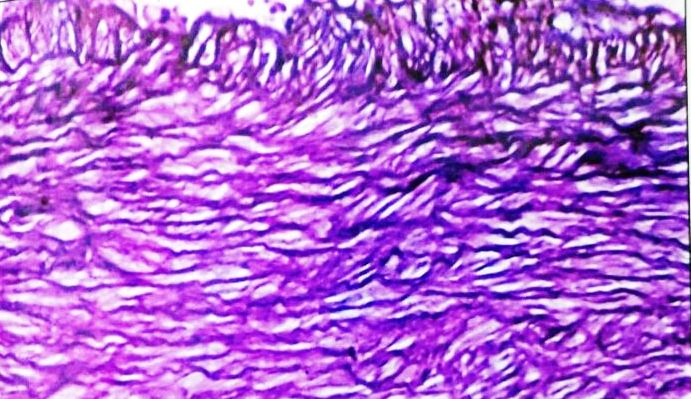

The histopathological examinations were also performed in the ascending aorta and coronary artery in high cholesterol animal diet group and high cholesterol animal diet accompanied with C. verum extract group when compared with control (fig. 3-10).

Asending Aorta

Histological study showed that control group had completely normal arteries without any lesion in intima or media. In our study athero fed rabbits showed well developed atheromatous plaque protruding in to the lumen of the aorta. There were many foamy (lipid-laden) macrophages and dense fibrous tissue layer in the plaque could be seen. Media was also showing foam cell. The animals consuming the C. verum along with high cholesterol, the severity of lesions were significantly reduced, three layers of aortic wall were distinct, and only few lipid-laden cells were present in the medial layer when compared with the rabbits consuming the high cholesterol diet (group II) (fig. 3-6).

Fig. 4: Ascending aorta of rabbit after Athero diet feeding for 120 d

Fig. 5: Ascending aorta of rabbit-Athero Diet+C. verum 200 mg concurrent (120 d)

Fig. 6: Ascending aorta of rabbit-Athero Diet+C. verum 300 mg concurrent (120 d)